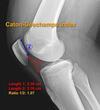

imaging for patellar tendon rupture: Insall salvation ratio > Blackburn-peel ration > caton-dechamps ration > ## Footnote "BIC 1,2,3"

Blackburne-Peel ratio > 1.0 Insall-Salvati ratio is > 1.2 Caton Deschamps ratio > 1.3 ## Footnote Insall-Salvati ratio is > 1.2, normal between 0.8 and 1.2 Blackburne-Peel ratio > 1.0 normal between 0.5 and 1.0 Caton Deschamps ratio > 1.3 normal between 0.6 and 1.3